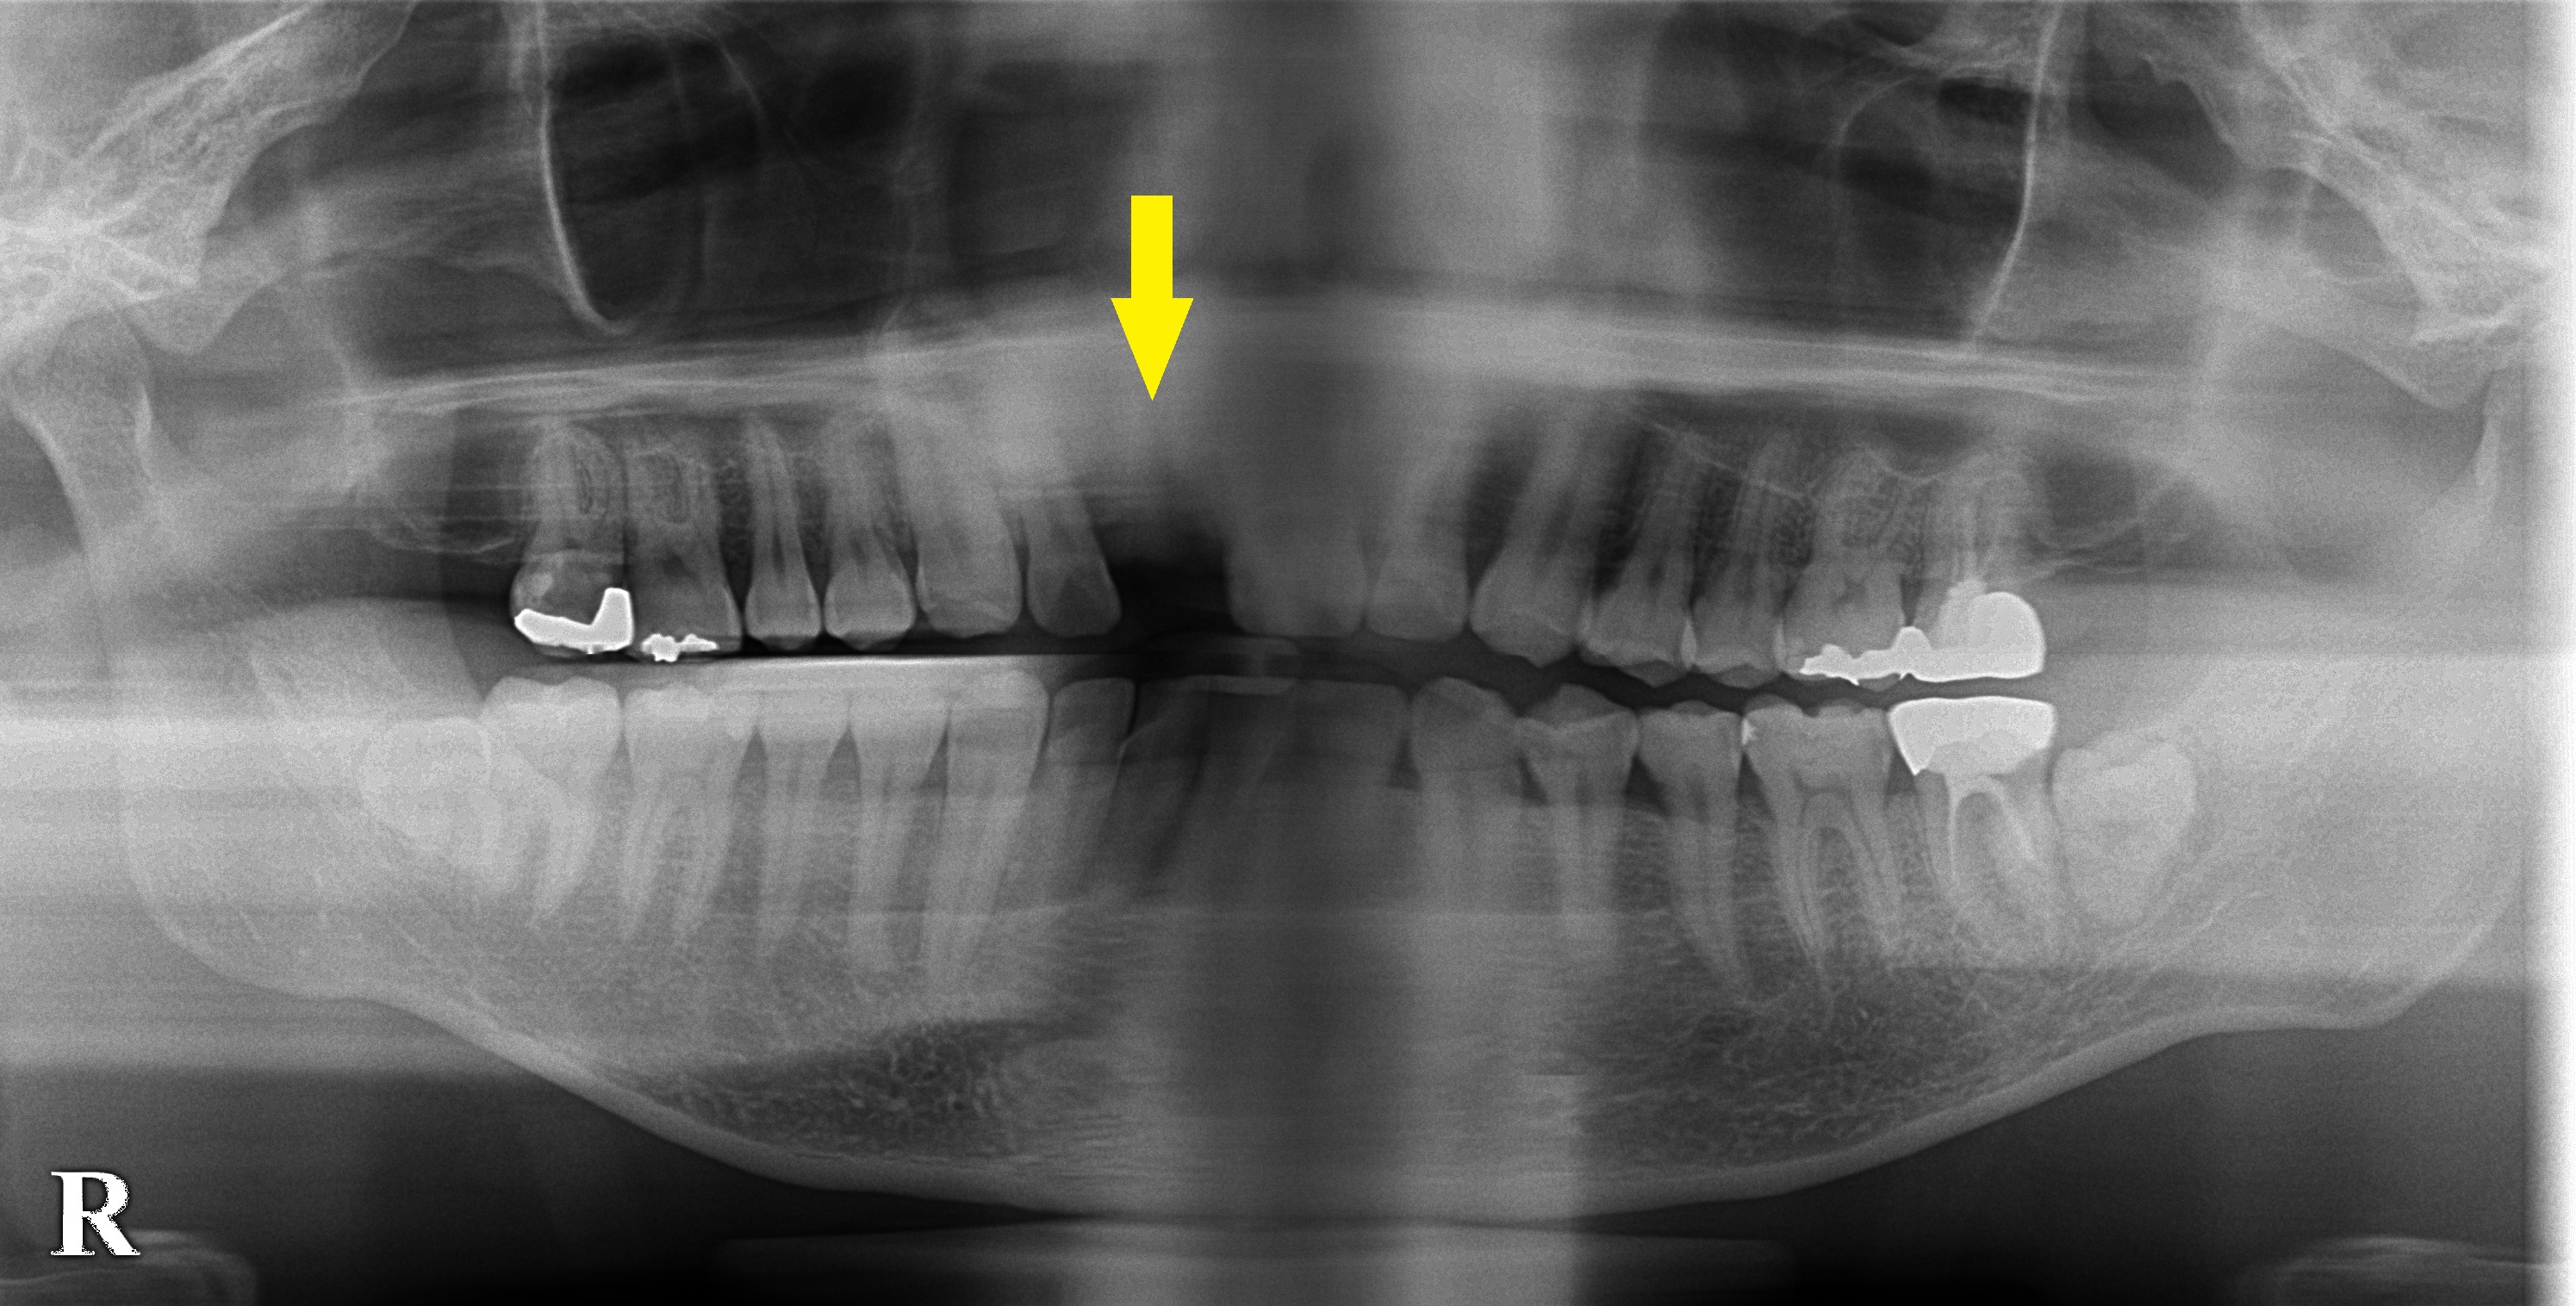

上顎前歯が1本抜けてしまいインプラント治療を希望された患者様です。

以前にご紹介したのですが、CTを撮ってみると、骨の厚みが4mm程しかないために(下段左の写真)、外側に人工骨を補填して骨造成を行い、インプラント埋入を行いました。

4か月経過し、上部構造を作製する時期がきましたので、術後経過観察のため再度CTを撮影させていただきました。

下段右の写真のように、インプラントの外側に、骨が確保され安定したインプラントの維持が可能になりました。